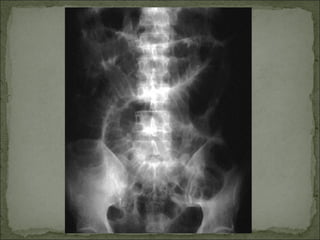

Dor em cólica; Distensão abdominal; Peristaltismo visível (ocasional); Desconforto à palpação; RHA aumentados em número e com alteração do timbre(metálico); Hipertimpanismo à percussão; Raio-X: distensão de alças com níveis hidroaéreos; Ex: obstrução de delgado (neoplasia, volvo, brida), cólica biliar ou renal

Dor em cólica;Distensão abdominal; Peristaltismo visível (ocasional); Desconforto à palpação; RHA aumentados em número e com alteração do timbre(metálico); Hipertimpanismo à percussão; Raio-X: distensão de alças com níveis hidroaéreos; Ex: obstrução de delgado (neoplasia, volvo, brida), cólica biliar ou renal